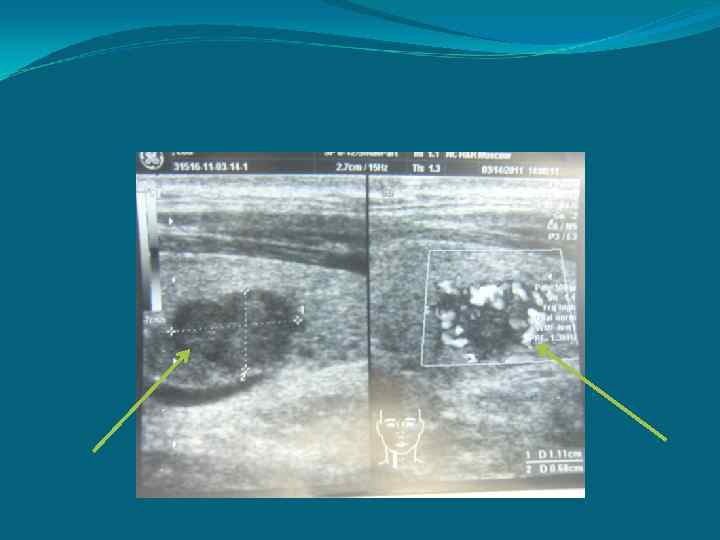

УЗ- исследование • Р-ры правой доли: • Р-ры левой доли: • Гипоэхогенное обрахование пр. доли , р-рами 0. 7*1. 2*0, 6 • Вторая доля не изменена 3 • Объем ЩЖ: 18 см

УЗИ + Доплер. картирование

ТАБ под контролем УЗи Цитологическое исследование( узел в правой доле ЩЖ) 2503 -11 5151 -6 -5157 пласты умеренно полиморфных клеток, принадлежащих солидному раку.